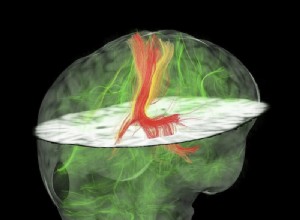

Prix Nobel de médecine 2014 : la découverte du « GPS interne » du cerveau